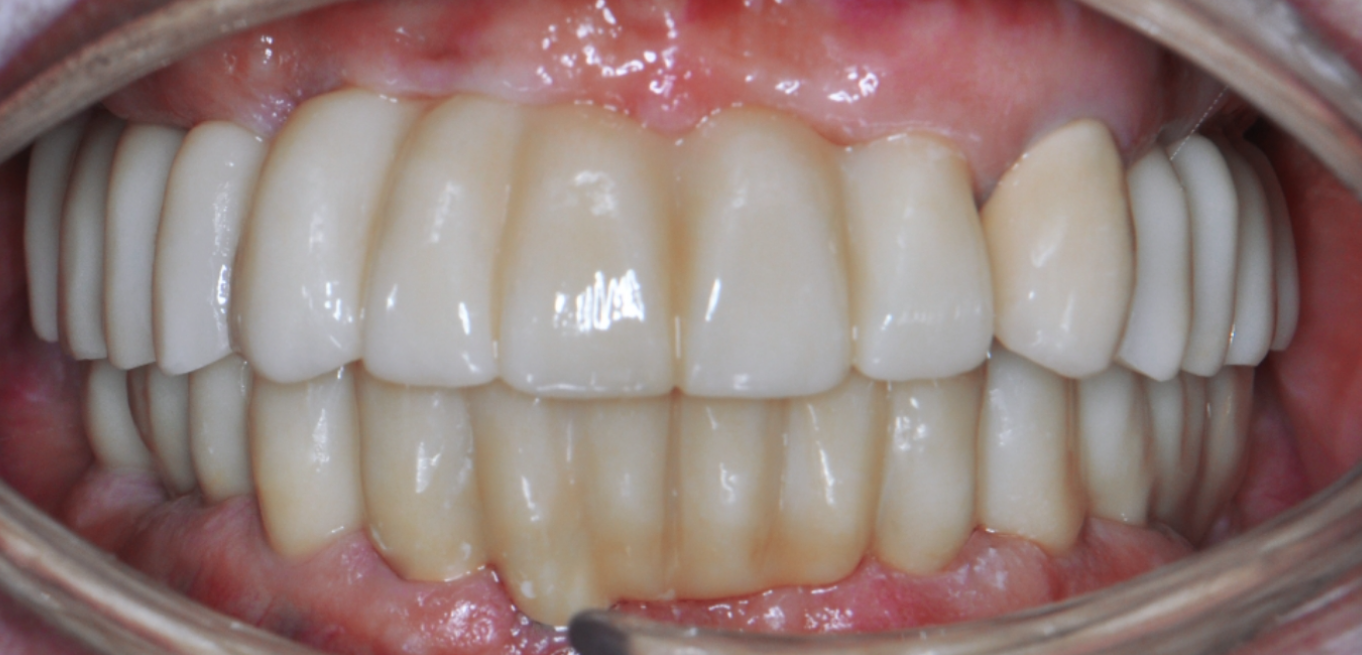

Before & After

Drag Before After

버튼을 움직여서 변화를 확인해보세요.

(서울정석치과는 의료법을 준수하며 위 케이스는 실제 환자의 동의를 얻은 사례입니다.)